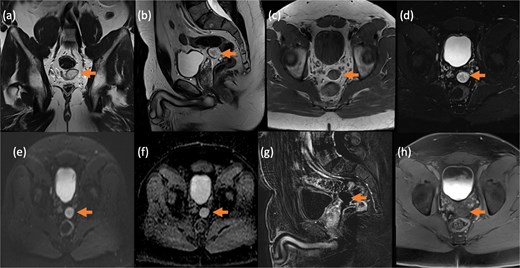

Pelvic magnetic resonance imaging (MRI) further characterized the pelvic lesion as a well-defined, non-enhancing, fluid-filled cyst measuring 3 × 2 × 1 cm without solid components, raising suspicion for pelvic hydatid seeding, although peritoneal inclusion cyst was also considered (Fig. 3). A 99mTc-dimercaptosuccinic acid (DMSA) scan showed preserved renal function with the right kidney contributing 25.7% of total function and a photopenic defect at the cyst site (Fig. 4). No other lesions were found on chest CT or brain MRI. Colonoscopy ruled out malignancy but revealed incidental low-grade adenomas.

Contrast-enhanced MRI of the pelvis in different sequences and different planes demonstrates a small, well-defined, oval-shaped lesion with high signal intensity on T2-weighted images (bold arrow—a and b) and low signal intensity on T1-weighted images (bold arrow—c). The lesion is located in the pelvis, inseparable from the seminal vesicles and the anterior rectal wall. It shows no signal drop on fat-saturated T2 sequence (bold arrow—d) no signify macroscopic fat, no restricted diffusion (dashed arrow—e and f) with T2 shine through, and no post-contrast enhancement on early subtracted (arrow head—g) and no delayed enhancement (arrow head—h). No solid component.